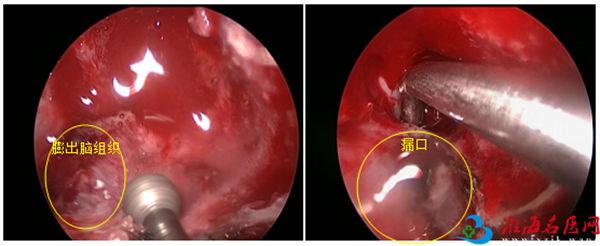

“这种疾病叫先天性脑膜脑膨出,属于神经管闭合障碍,由于先天性颅底发育异常致颅底脑膜脑膨出,长时间的膨出组织挤压使颅底骨质出现漏口,引起自发性脑脊液鼻漏。你的漏口需要手术进行修补,但是目前先要抗感染治疗。”听完徐主任的讲解,L女士和家人才恍然大悟。

跨专科协同手术,成功堵漏

病因查明后,治疗就有了方向。经过积极治疗,L女士颅内感染症状得到控制,手术也排上日程。由于漏口位于蝶窦外侧隐窝,靠近颈内动脉,徐锋启动了鼻眼、鼻颅多学科会诊。专家组讨论后决定由神经外科和耳鼻咽喉科联合进行手术,利用神经导航微型手术机器人系统进行漏口的实时定位,经鼻微创入路在内镜下进行脑脊液鼻漏修补术,将手术创伤降至最低。

手术当天,在麻醉团队戴必照、卢思宇、孙媛媛和护理团队周慧、杨依心的密切配合下,徐锋和团队成员副主任医师张继东、主任医师朱保平,耳鼻咽喉科副主任、主任医师王浩联合为患者实施了手术,成功修补了漏口。